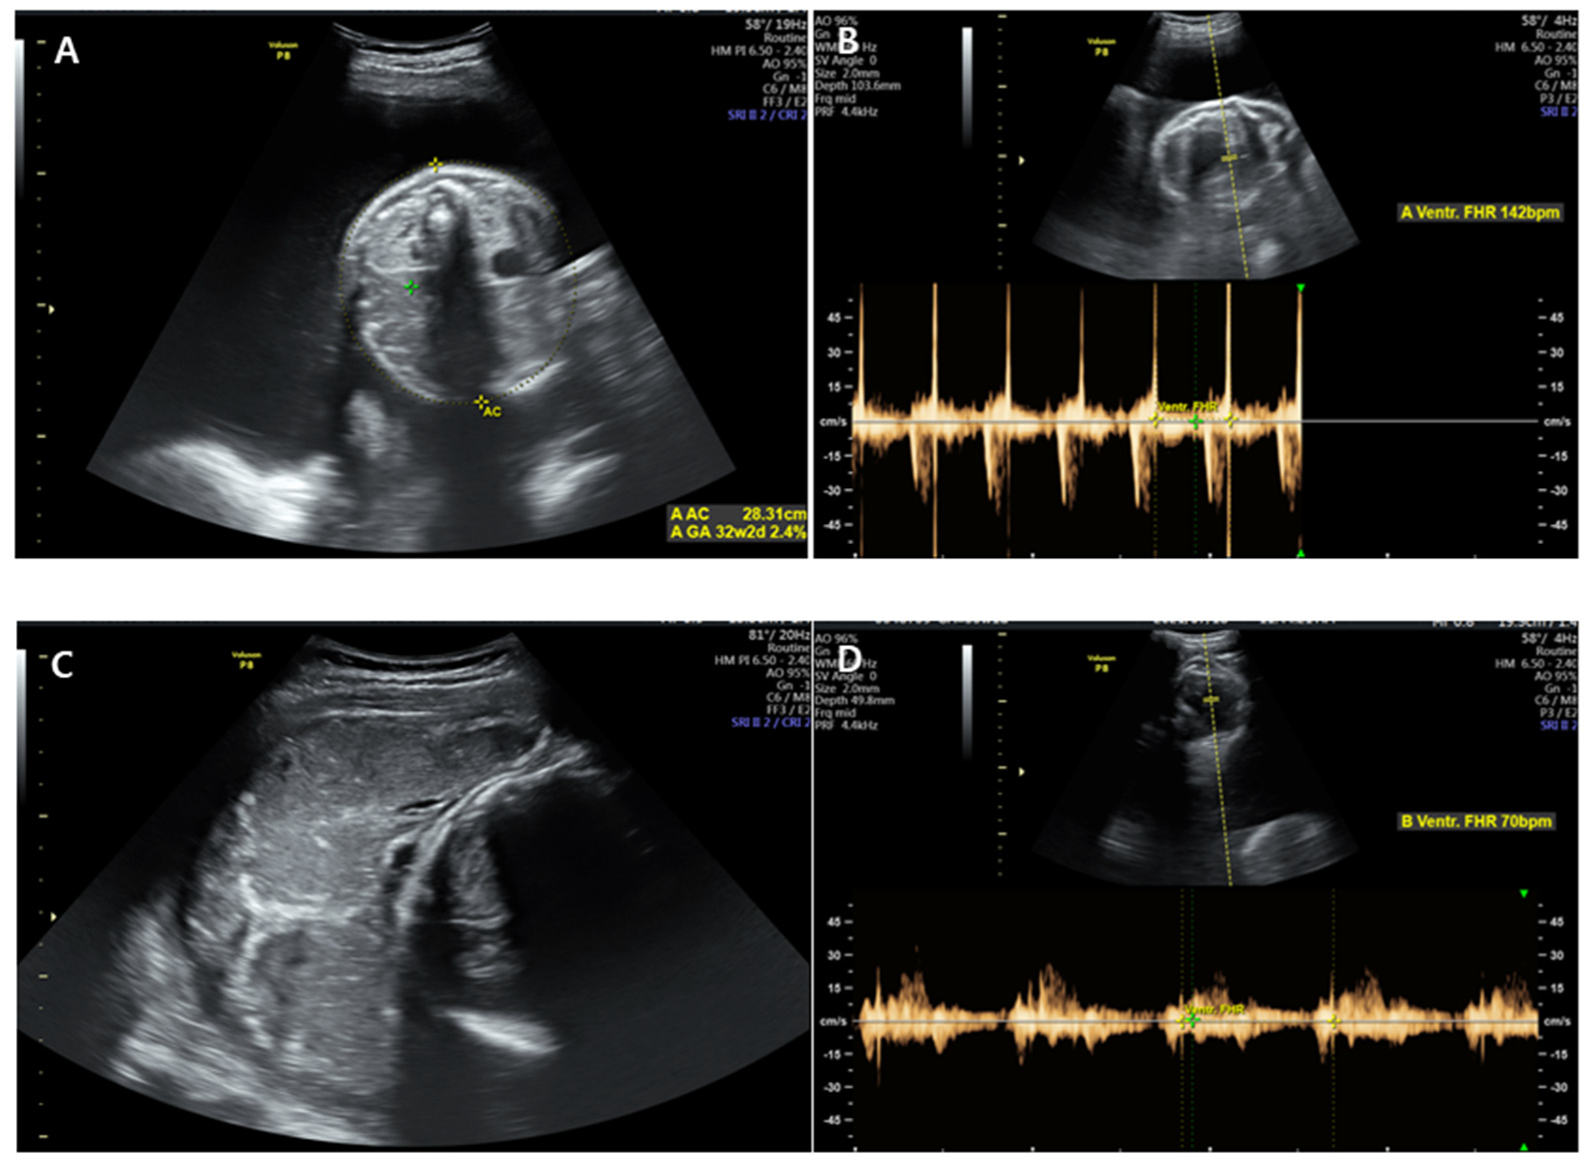

Figure 1. An ultrasonographic examination at 6 days before visiting emergency room. The intertwine membrane (yellow arrow) was well seen, and the amniotic fluid of both fetuses was normal.

A 28-year-old pregnant woman (gravida 1, para 0), who had attended regular prenatal checkups at our hospital outpatient clinic, visited our emergency room at 35 + 1 weeks of gestation because of persistent uterine contractions for 3 h. She felt fetal movements relatively distinctly and experienced no other obstetric problems such as vaginal bleeding or a vaginal watery discharge. She reported that she had felt her abdomen suddenly enlarge two days before, and that from then on, her dyspnea seemed to worsen. Her medical history was unremarkable, and her pregnancy had involved a spontaneous monochorionic diamniotic twin gestation. Amniocentesis had been performed because of the high risk of Down syndrome in the integrated test, but the patient had been diagnosed with a normal karyotype, and there were no structural abnormalities on detailed ultrasonography at 20 weeks of gestation. Ultrasonographic findings showed no marked differences in weight between the two fetuses and no significant differences in the amniotic fluid volume; therefore, the possibility of chronic TTTS was considered low. However, a short cervix was confirmed and a progesterone vaginal tablet was used. Growth delays were observed in both fetuses from 29 weeks of gestation, but there were no specific findings in infectious serum markers for congenital infections, and no significant problems in the umbilical artery, middle cerebral artery doppler, and amniotic fluid volume were observed. Serial ultrasonography was consequently performed every week. And, an ultrasound examination performed at an outpatient clinic 6 days before visiting the hospital showed an intertwin membrane, and the amniotic fluid volume were normal in both fetuses (Figure 1).